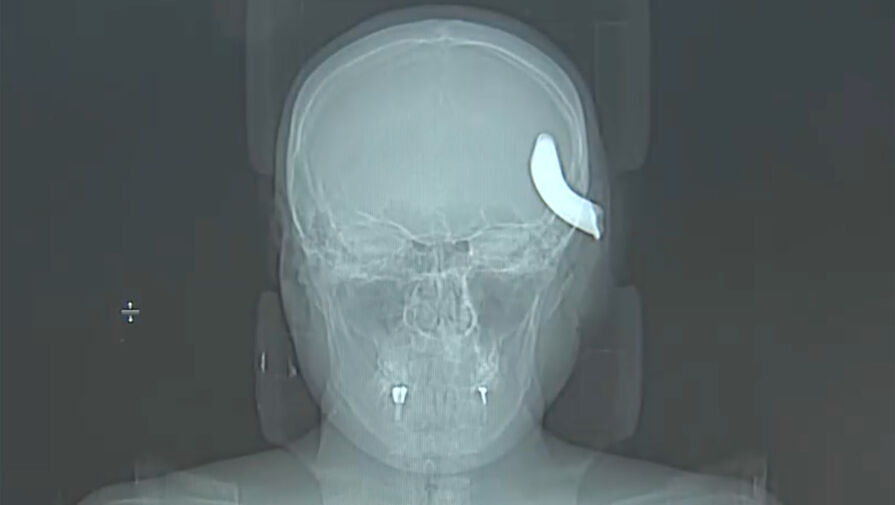

Российские врачи спасли мужчину с крюком в голове. В Санкт-Петербурге врачи Елизаветинской городской больницы спасли 34-летнего мужчину, которому в голову вошел металлический крюк. Об этом врачи больницы рассказали в беседе с журналистами телеканала "Санкт-Петербург". Инцидент, ...